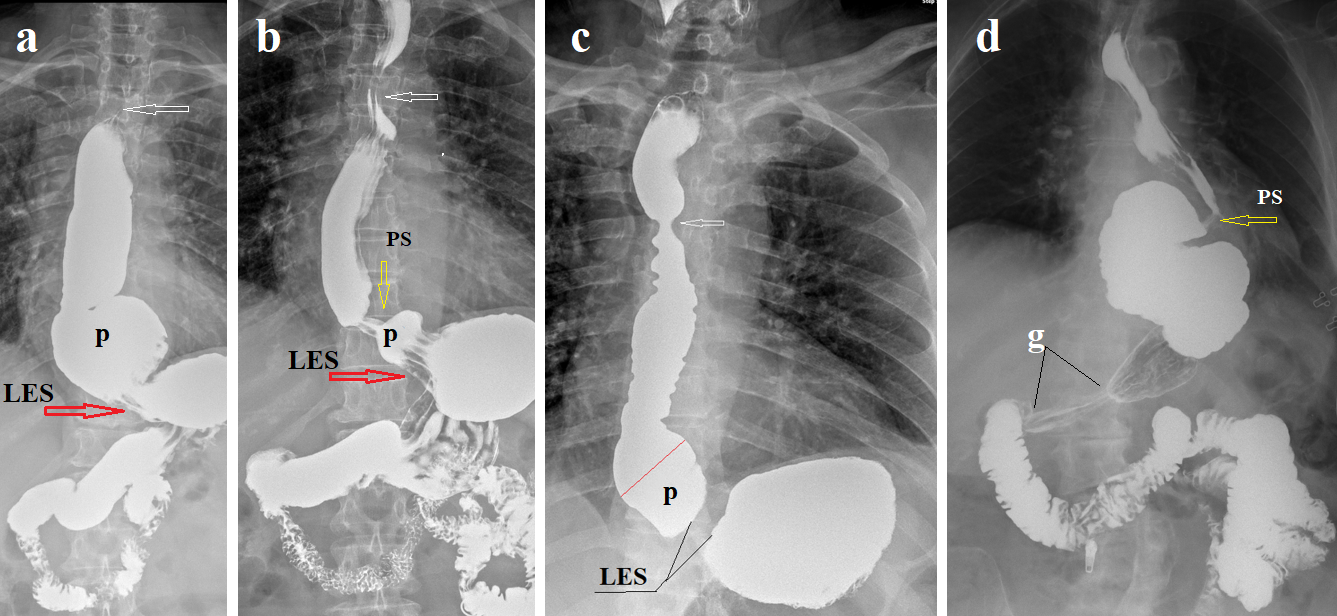

Figure 1. Esophageal radiographs are taken at high gastric pressure. Red arrows indicate the LES, yellow arrows indicate the proximal sphincter, which proximally closes the phrenic ampulla (p); white arrows indicate the aortic sphincter, which occurs because of acid retention in ​​esophageal constriction at the level of the aortic arch. (a). At high pressure, the contracted LES does not close the EGJ. (b). The same patient. After 5 minutes of resting, free reflux is determined. The LES is shortened, and the hiatal orifice is dilated. Due to chalasia of EGJ, the patient feels heartburn as soon as acid appears in the stomach. (c). A patient with severe esophagitis with only extraesophageal symptoms. The length of the LES is more than 2 times shorter than the minimal normal limit. He wakes up at night because he chokes on saliva. This is due to the contraction of the aortic sphincter. After he swallowed a dense tablet with a diameter of 1.9 cm, almost all symptoms disappeared. The absence of pain syndrome indicates damage to the sensitive elements in the wall of the esophagus. (d). S-shaped esophagus in an elderly woman after Nissen fundoplication. The esophageal dilation has developed over the overly compressed LES. The red arrow shows the narrowing, which is mistakenly called the LES, displaced into the chest cavity. This is the proximal sphincter, the contraction of which closes the lumen of the phrenic ampulla proximally to create a high pressure in it, exceeding the pressure in the stomach. The long rigid antral gastritis (g) shows that hypersecretion of hydrochloric acid is not only a problem of the esophagus.

This description of the pathogenesis of lactose intolerance contains two hypotheses. The first hypothesis is assumed that lactase is fermented in the colon by bacteria to form carbon dioxide, hydrogen, methane, proprionic and butyric acids. The second states that symptoms occur because of lactose fermentation by bacteria in the colon. The first hypothesis is confirmed by the increase in expired hydrogen and methane during the lactose breath test [4-6]. The second contradicts the clinical picture. Infants react to pain with anxiety, so it is impossible to assess their symptoms and the time of their appearance. In adult patients with lactose intolerance, in the presence of cardia dehiscence, when the contents of the stomach enter the esophagus immediately after eating, heartburn appears 15-30 minutes after drinking even a small amount of milk in a cup of coffee. Since the contents of the stomach enter the large intestine no earlier than 4.2 hours later [7], and lactose fermentation occurs gradually during slow movement through the large intestine, therefore, the appearance of heartburn after 15-30 minutes occurs under the action of another mechanism. Deng et al. found in adults that with “true positive” lactose intolerance complains of symptoms only after the substrate has entered the colon (usually 50–100 min). The difference in the time of symptom onset depends on the degree of damage to the LES. With complete failure of the LES (chalasia of EGJ) (Figure 1a & 1b), gastric chyme enters the esophagus immediately after lactose ingestion. This means that excess acid occurs in the stomach after 15–30 minutes. If the function of the LES is weakened to a lesser extent and it opens sometime after lactose ingestion, the patient does not associate the occurrence of heartburn with lactose ingestion. Figure 1d shows an X-ray of a patient after the Nissen fundoplication. The patient suffered from frequent severe heartburn, despite taking PPI. Heartburn temporarily disappeared only after drinking milk, since milk, being a base, neutralized the acid. After she stopped drinking milk, heartburn became rare and short-lived [8].